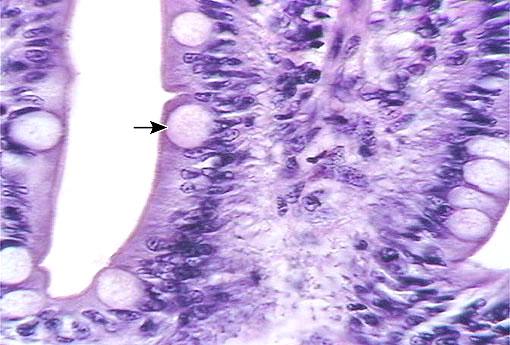

Goblet cells

arrow

Microvillus (s.) Microvilli (pl.)

small intestine model